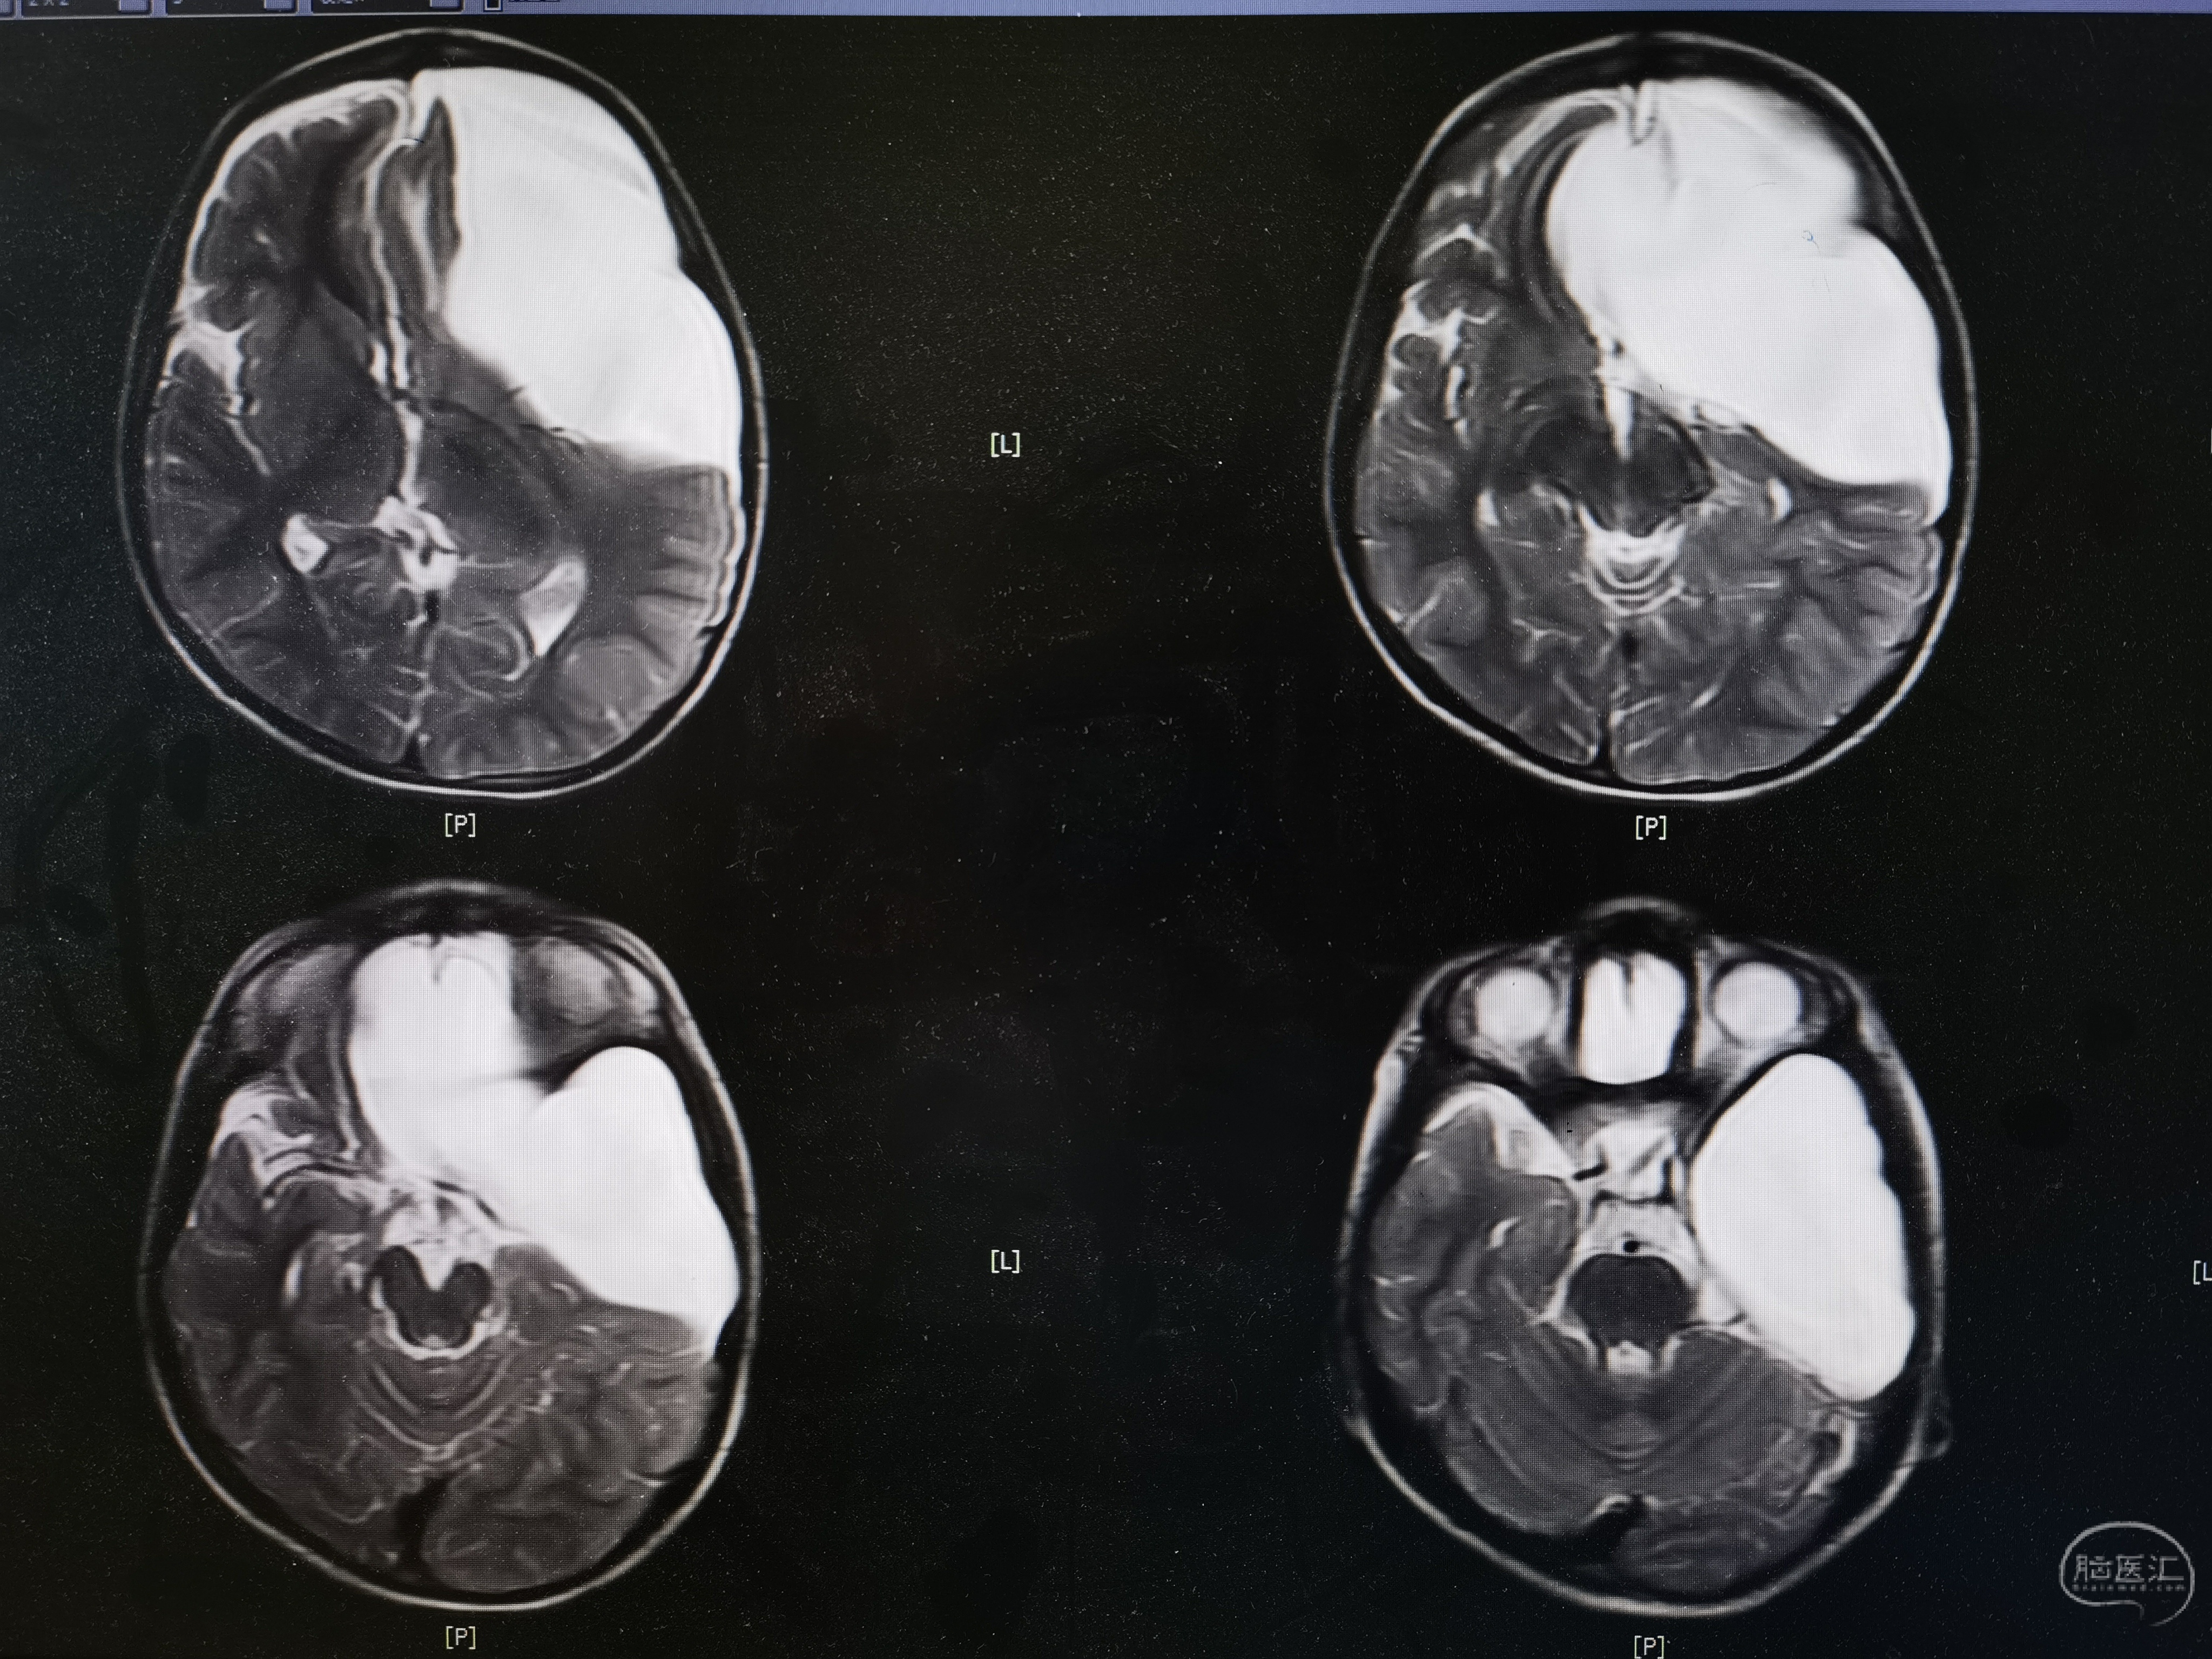

8岁男孩,以“头部外伤后头晕8天”入院,患儿8天前于3米高处坠落摔伤头部,伤后有昏迷史,当地医院CT提示左额颞巨大蛛网膜囊肿,破裂可能。患儿伤后感头晕,当地医院建议转至我院。我院完善头颅MR提示左额颞巨大蛛网膜囊肿,局部越过中线突入右侧镰旁挤压右额叶,左侧额颞岛叶明显受压,囊肿破裂可能。

术前MR